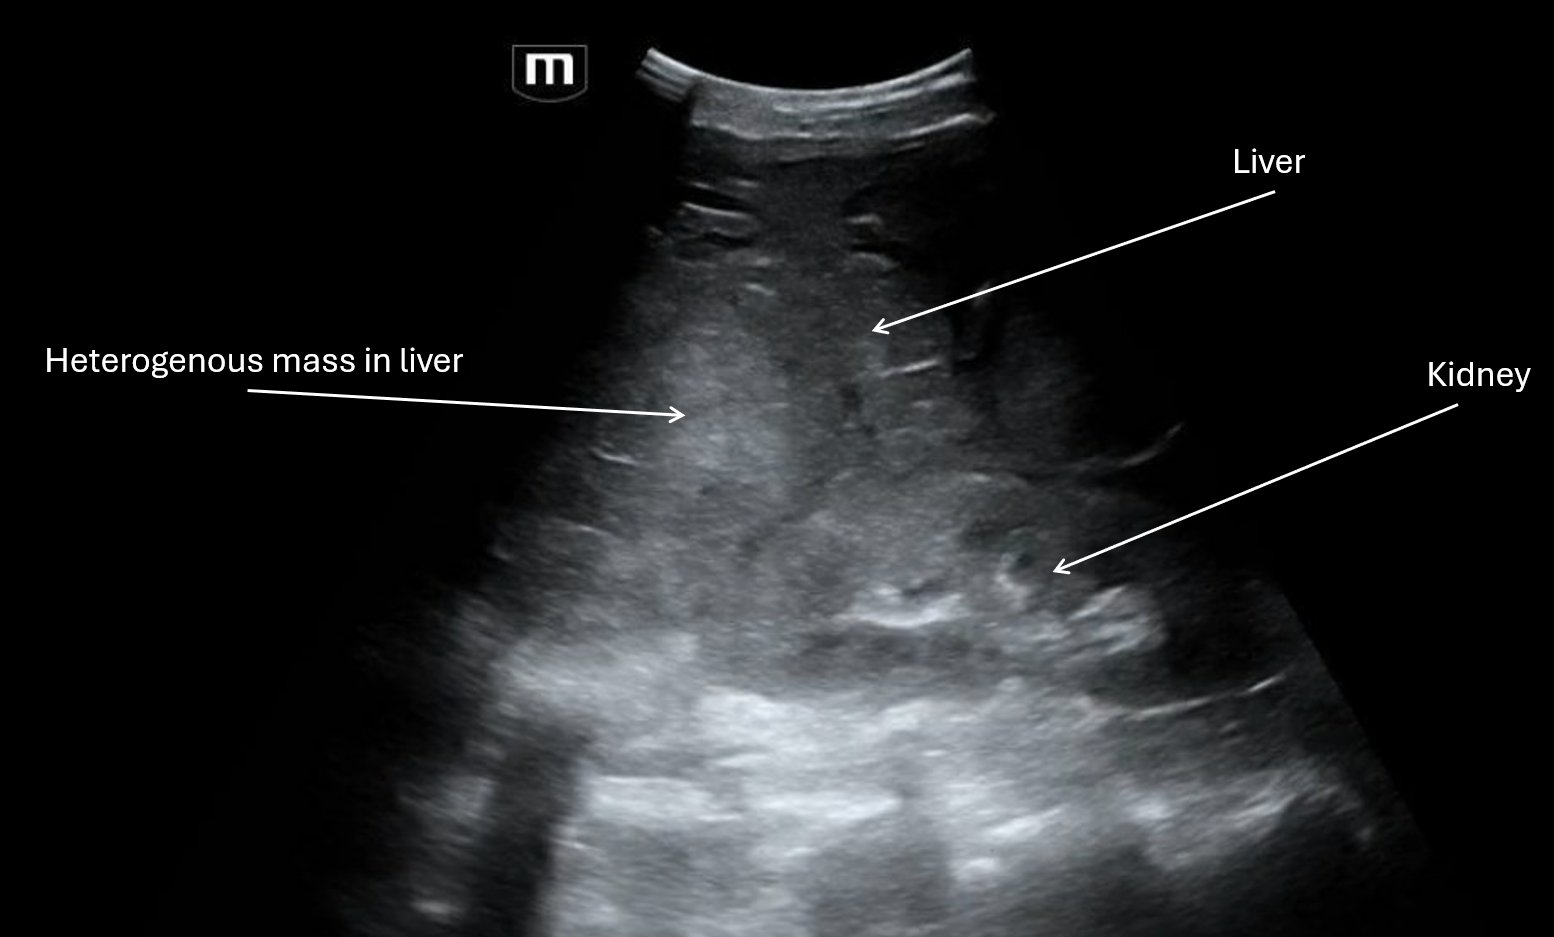

The team did a FAST and here are some labeled images from their respective clips:

Clip 2 shows a RUQ view with the liver that appears to have a heterogenous mass.

From the imaging, patient may have liver cancer, and the trauma from the fall seemed to have caused the masses to bleed and cause large volume hemoperitoneum. IR wasn't able to identify the exact vessel that had been bleeding but empirically embolized the right hepatic artery. A total of 2 liters of bloody fluid was drained from the abdomen.